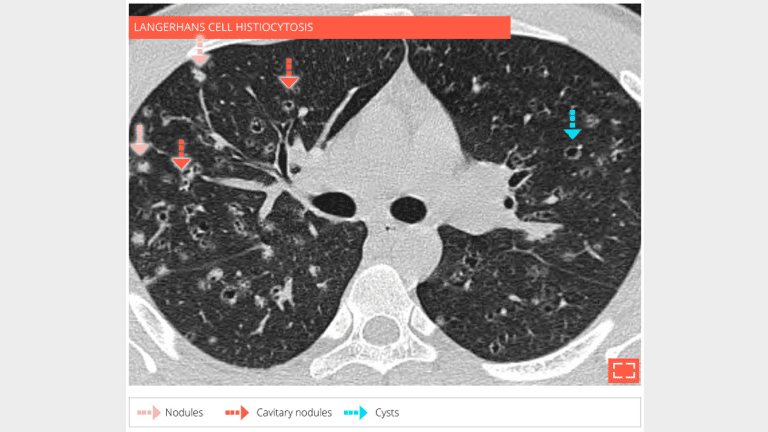

HRCT at the level of the upper lobes shows numerous micronodules, cavitated nodules, and cysts in a 32-year-old man curent smoker who developed langerhans cell histiocytosis.

The patient is a 28-year-old male, smoker, with langerhans cell histiocytosis. HRCT at the level of middle zone shows bilateral and symetrical abnormalities of the lung parenclyma consisting in nodules, cavitated nodules, and cysts.